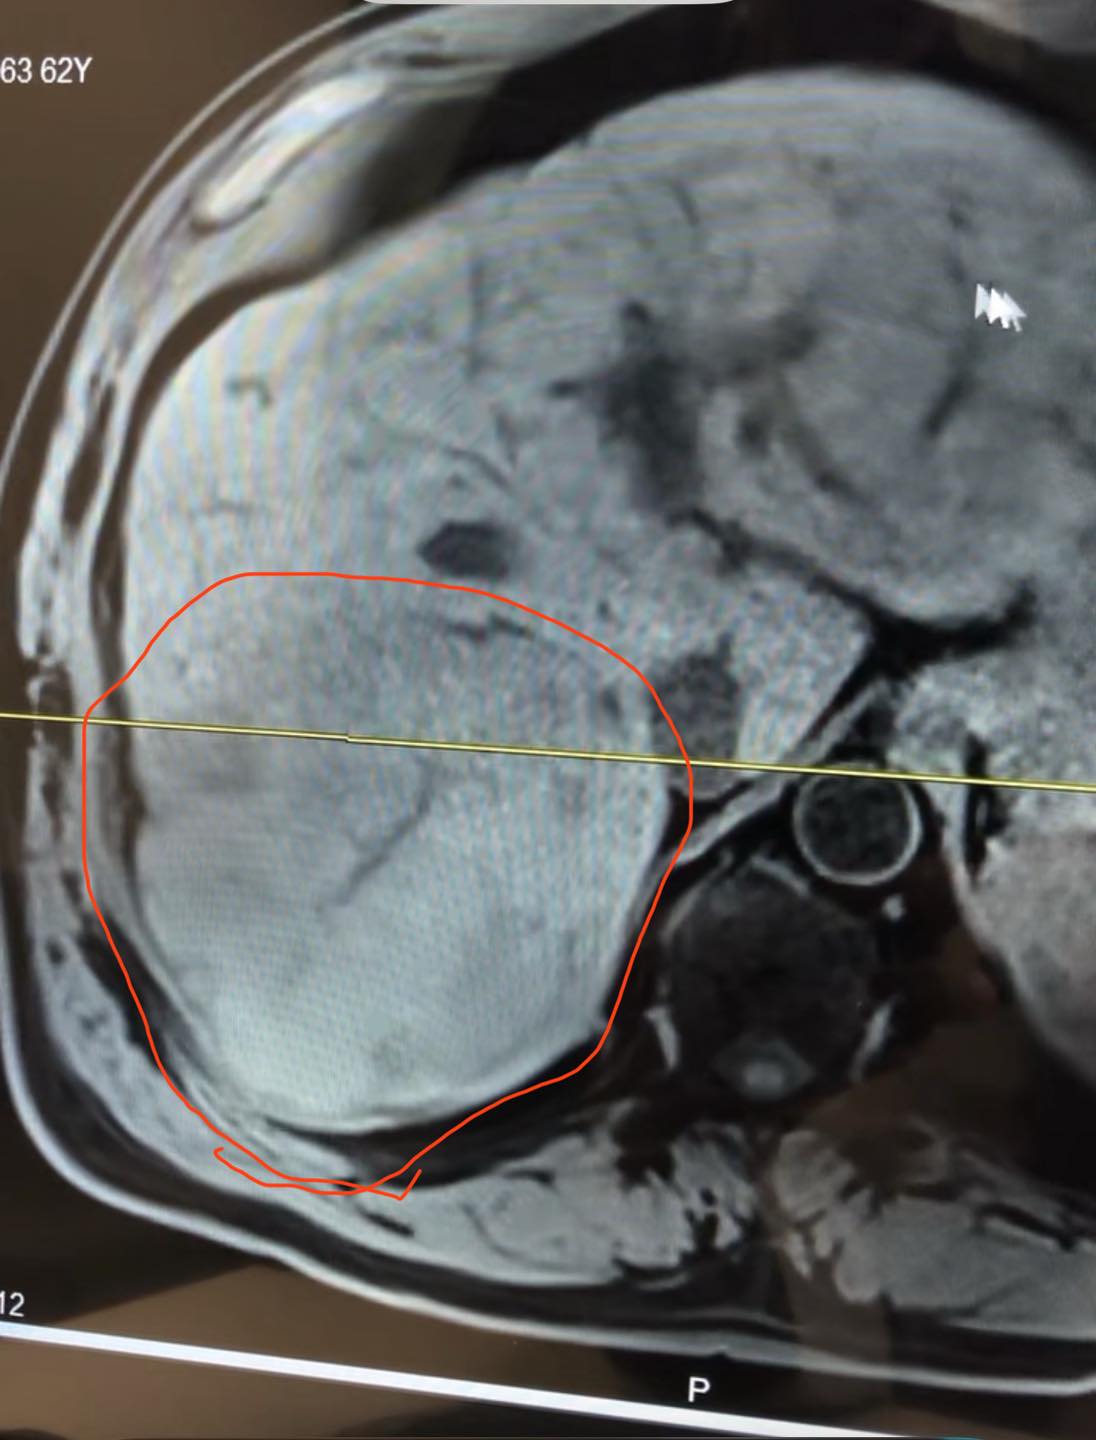

Note: this is a picture of Keith’s liver. The tumor is circled in red.